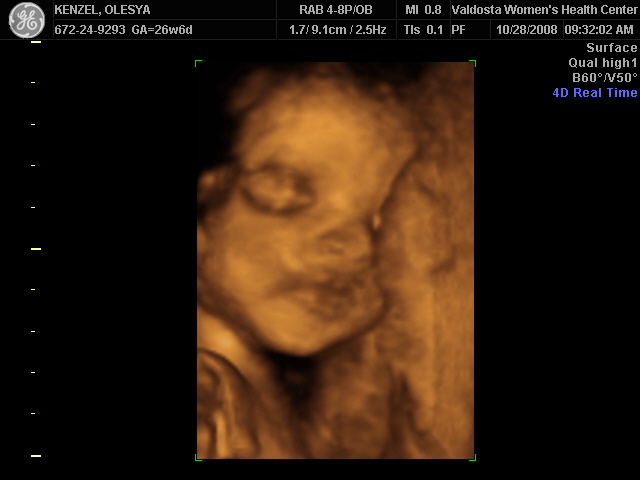

Ксюнь, а мы вообще не поняли. Она на всех фотках разная, да еще размытость такая. Пуповина то на носу болталась, то руками-ногами закрывалась. Главное что четкости нет совсем. Лоб у мужа тоже большой, а носы и губы зачастую на 3Д-4Д выходят разамазанно-пухло-приплюснутыми Поставлю для наглядности фотку моей средней-Джианки с 3Д УЗИ, там видно черты намного лучше и она на себя ту похожа сейчас, хотя родилась мне совсем на фото УЗИ не казалась похожей.

| Вложения: |

KENZEL,OLESYA_3.JPG [ 56.84 КБ | Просмотров: 1404 ]

Еще одна Джианнка:

KENZEL,OLESYA_5.JPG [ 60.02 КБ | Просмотров: 1489 ]

Катюш, какой прикольный бутузик ! Олесь, после фотки средней - точно прям похожи!